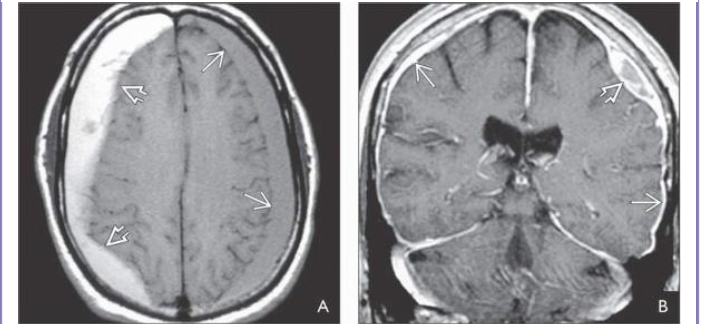

What sequence?

What is shown?

FLAIR scan in a patient 2 days after closed head trauma shows a small hypodense SDH and multiple

axonal injuries